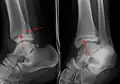

-

A triplane fracture of the ankle as seen on plain X-ray -

- Triplane fractures are a special type of fracture that involves the immature skeleton. It has a coronal plane in the metaphysis, an axial plane in the physis, and a sagittal plane in the epiphysis.[15]